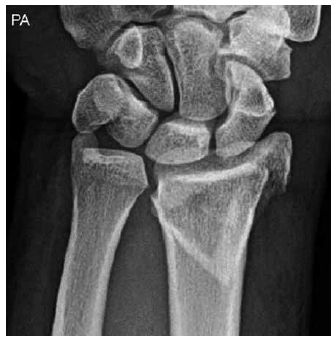

Radiografias em PA e perfil do punho de paciente masculino, 54 anos, com queda com a mão espalmada, praticando atividade esportiva.

A fratura do rádio mostrada nas imagens pode ser classificada como fratura de